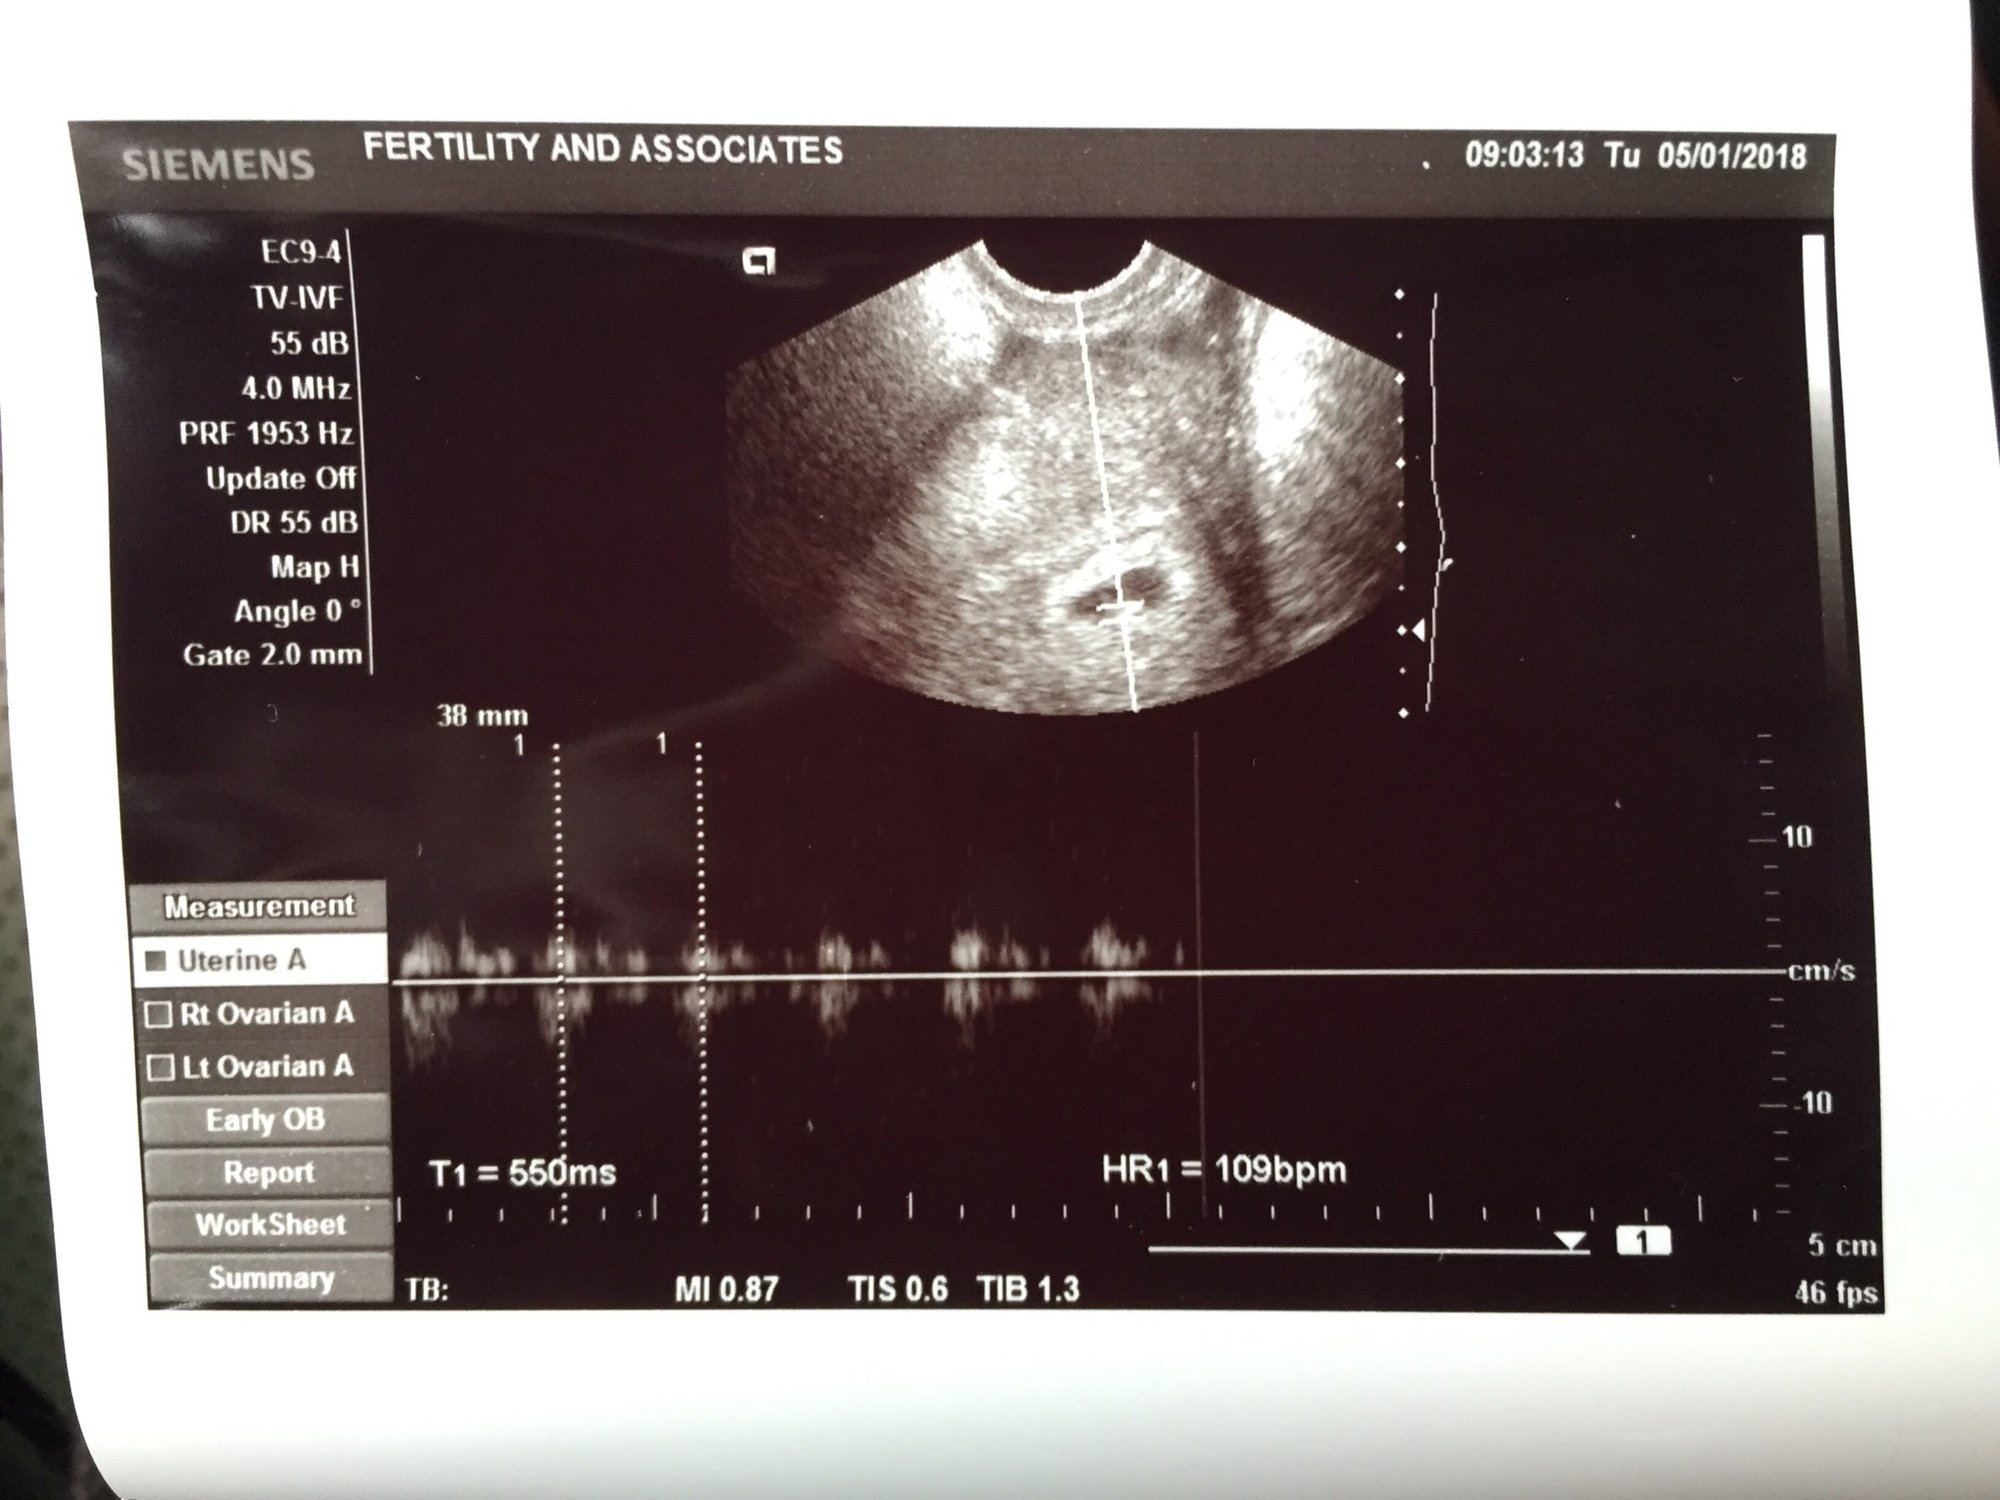

We have a heartbeat! I was so, so anxious this morning.

109 (ref range for now 80-120). She measured 5.3mm one time and 4.7mm another. One week at a time...